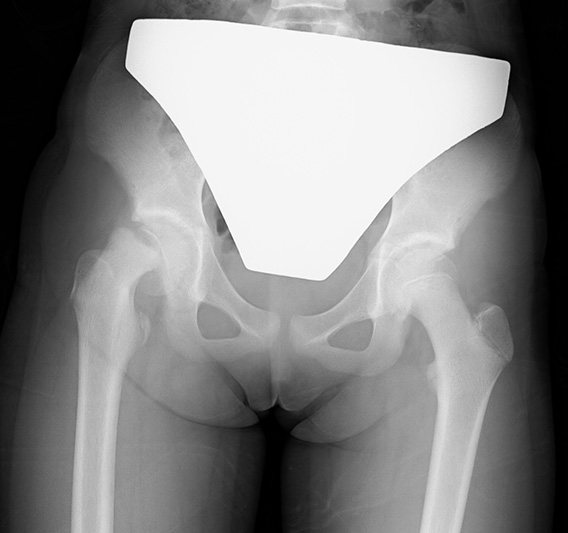

二分脊椎

胎児期の脊髄や脊椎の癒合不全が残ってしまい,運動や知覚,排尿や排便機能などの神経機能に程度の差はありますが異常を来す疾患です。小児科,脳神経外科,泌尿器科,整形外科やリハビリテーション科などが関わり治療をすすめます。整形外科的には脊椎,股関節や足部が麻痺による筋力バランス不良などによって生じた変形に対し,残った機能をできるだけ活用できるようにしています。

・治療法

短下肢装具や歩行訓練用の骨盤帯付き長下肢装具を用いて日常生活やリハビリテーション治療が効果的に行えるよう支援します。

変形が強く装具が装着できなくなった場合や,脱臼により股関節の安定性が不良な場合は手術療法を行っています。

短下肢装具と骨盤帯付き長下肢装具

両麻痺性股関節脱臼に対して骨切り術を順次両側に行いました。